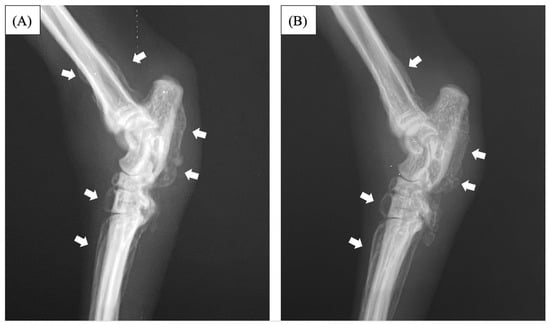

2. Case Description